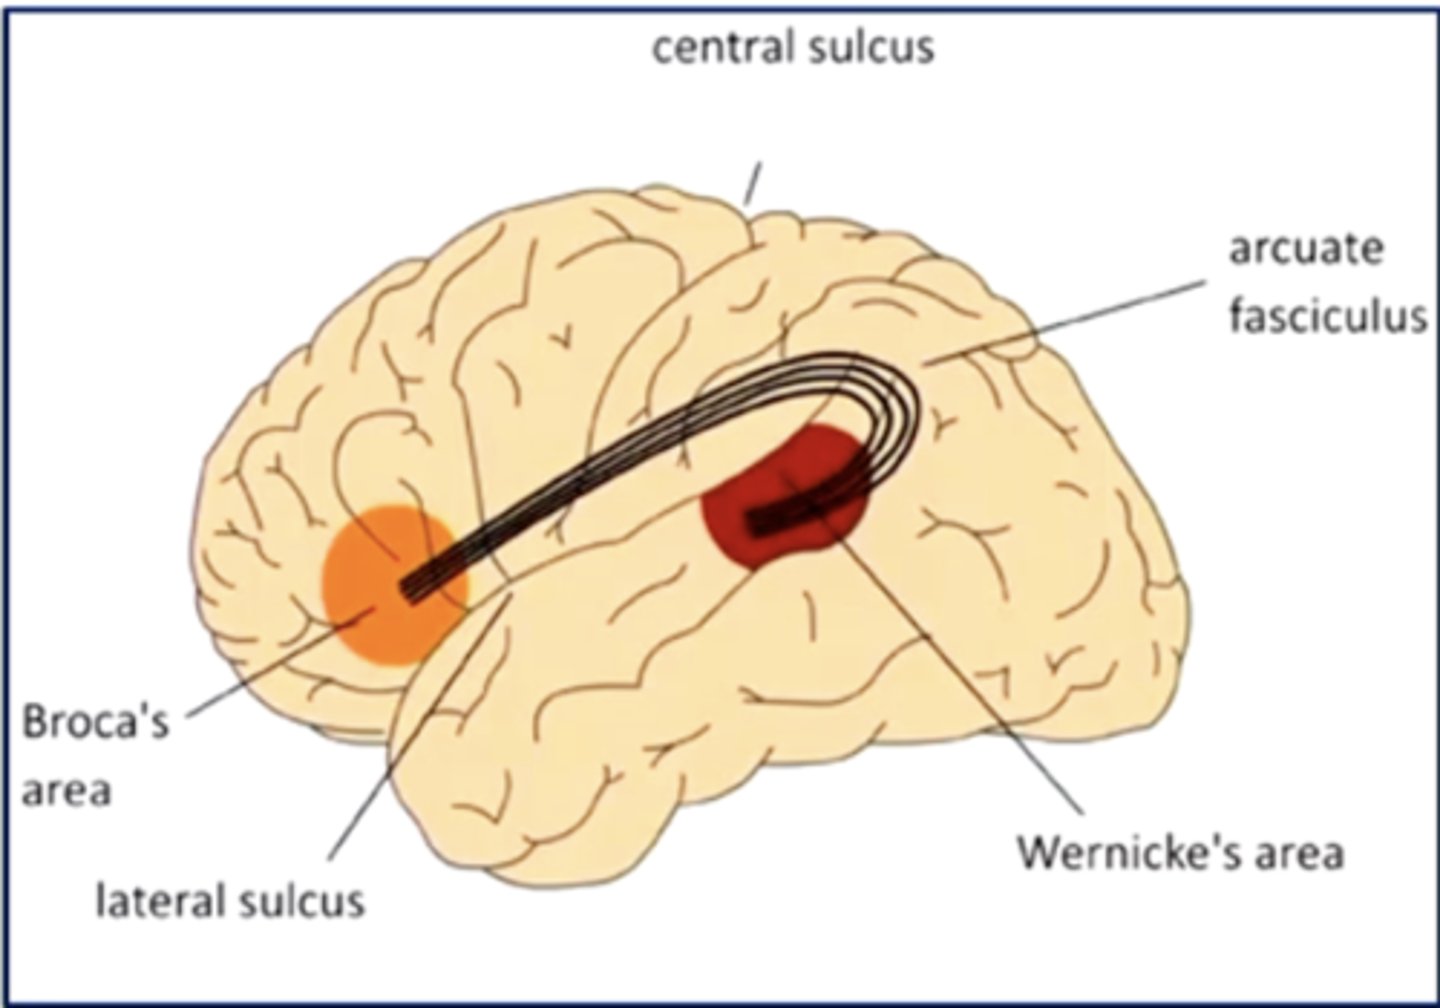

list the cortical region and cerebral lobe of the speech/language system:

cortical region:

Broca's and Wernicke's areas

cerebral lobe: frontal (Broca's) and temporal (Wernicke's)

Broca's and Wernicke's areas are located on the (left/right) hemisphere of the brain in most people

left

a good guess to where the language centers are is based on your dominant hand (right hand dominant --> language centers will be in the left hemisphere)

what is Broca's area?

area in the frontal lobe responsible for language production (speaking, writing, signing)

a lesion in Broca's area could result in what?

Broca's aphasia

results in slow, labored speech, agrammatism (lacking correct grammar), and anomia (inability to name objects)

understanding is good, finding/creating the words is difficult

what is Wernicke's area?

area in the temporal lobe responsible for language comprehension (speech, written language, sign language)

a lesion in Wernicke's area can result in what?

Wernicke's aphasia

person can produce fluent speech/language, but it is meaningless ("word salad")

language production is there, it just makes no sense

what is the arcuate fasciculus?

an axonal pathway that connects Wernicke's area to Broca's area

cell bodies are in Wernicke's area, and axons synapse in Broca's area